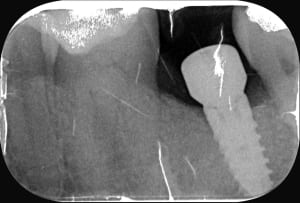

558904719_10163144646272247_6774572045327740986_n.jpg